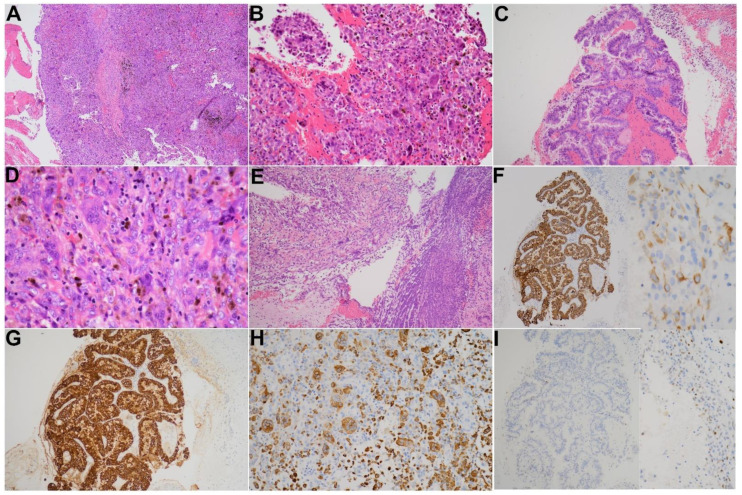

Grossly, a bloody mass composed of a mixture of tissue debris, blood clots and pus was extracted from the bile ducts. Pathology revealed a tumor consisting of three cell types including osteoclast-like multinucleated giant cells (OGCs), mononuclear histiocytes and neoplastic mononuclear cells in a background of extensive hemorrhage and deposition of hemosiderin pigments (Figure 4A–D). Foci of tissue necrosis and inflammatory exudates were noticed (Figure 4E). A microscopic focus of malignant epithelia exhibiting papillary and tubular glandular structure floating in the blood clots was found (Figure 4C). There was no microscopic evidence of tumor invasion to the stroma of the bile duct.

Immunohistochemistry (IHC) was performed on selected blocks and showed that malignant epithelia were highlighted by AE1/AE3 (Figure 4F) and CK19 (Figure 4G). Weak positivity was also observed at some atypical mononuclear neoplastic cells. The osteoclast-like giant cells and histiocytic mononuclear cells were positive for CD68 (Figure 4H). P53 was expressed in few neoplastic cells (Figure 4I).

Pathologically, the characteristic picture of UCOGC has been well documented [ref. 16,ref. 20,ref. 25]. In most cases, the compact and cellular neoplasm resembled giant cell tumors of bone in a background of hemorrhage and deposition of numerous coarse hemosiderin pigments. The tumor was composed of three distinct cell populations: OGCs, mononuclear histiocytes and mononuclear carcinoma cells. The OGCs displayed the characteristic features of this cell type seen in the bone, including large cells with acidophilic cytoplasm and multiple uniform nuclei, usually clustering in the central aspect of the cell. The OGCs showed positive immunoreactivity for CD68 but a lack of reactivity for epithelial markers. They were commonly found in areas adjacent to the hemorrhage and necrosis. The mononuclear histocytes, as the name implies, had monotonous single nuclei and were immunoreactive for histiocytic marker CD68. Epithelial markers such as cytokeratin were generally negative in mononuclear histiocytes. The mononuclear neoplastic cells, on the contrary, were positive for cytokeratin, confirming biliary epithelial origin. The neoplastic cells were spindly to squamoid in appearance and could demonstrate varying degrees of cytologic atypia and mitotic activity [ref. 16,ref. 20,ref. 25]. As studies presumed that tumors containing osteoclast-like giant cells spanned the spectrum from truly benign giant cell tumors to highly lethal anaplastic spindle and giant cell carcinomas, careful histologic and cytologic examination and IHC studies were recommended [ref. 16,ref. 27].